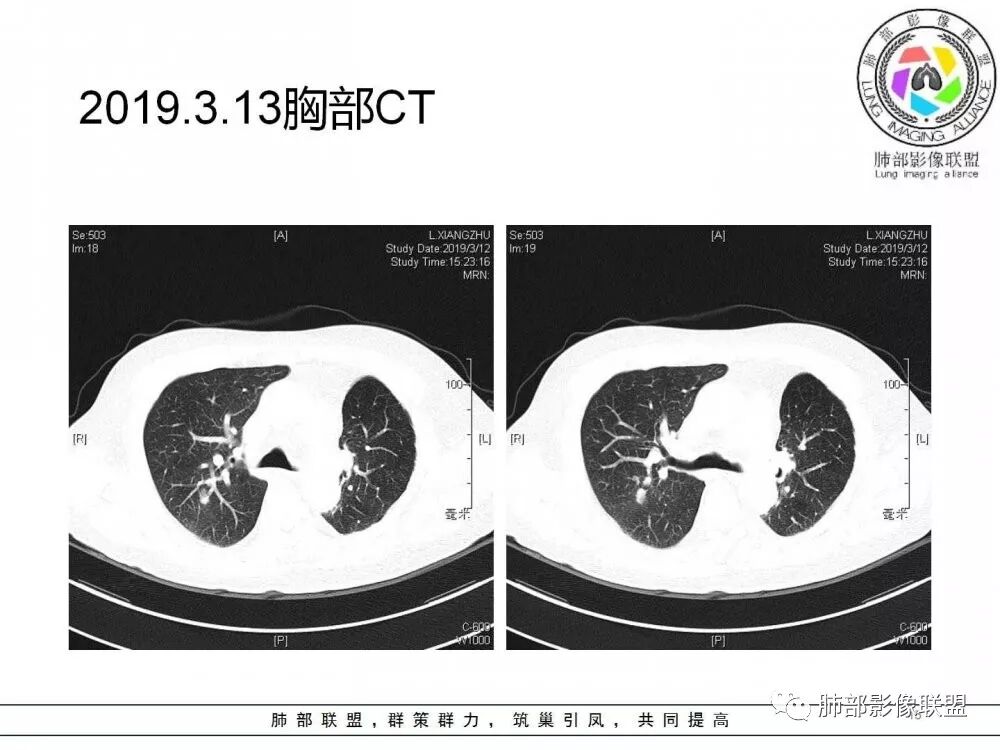

右肺上叶后段实性结节,部分边缘磨玻璃,周围可见多发小结节,病灶逐渐进展,临床有肺癌病史、LGG4相关病变、激素长期使用史,考虑1隐球菌。2肺癌复发。3LGG4相关性肺改变,病变局限,应该不符合。

右肺上叶后段多发实性结节,边缘收缩,葫芦兄弟,临床有激素治疗史,考虑隐球菌。

肺癌病史,长期激素实用史,IgG4相关病史,治疗有抗癌和激素治疗,肺部多发胸膜下小结节,边缘模糊,有些结节有进展,葫芦兄弟,考虑隐球菌。

右肺上叶后段实性结节,周围可见多发小结节,病灶逐渐进展,临床有肺癌病史、LGG4相关病变、激素长期使用史,考虑1隐球菌。2肺癌复发。3LGG4相关性肺改变

病例1右肺上叶后段实性结节,部分边缘磨玻璃,周围可见多发小结节,病灶逐渐进展,临床有肺癌病史、LGG4相关病变、激素长期使用史,考虑1隐球菌。2肺癌复发。3LGG4相关性肺改变,病变局限,应该不符合。(临床小白,纯属蒙)

病灶从2月份就开始有,应该最早说是1月7号就有了,到3月13号稍微增大一点,到后面几乎没变化,到5月份好像稍微大一些,炎性应该是炎性,犹豫的是这个炎性到底什么病变呢?其实本没变化,它特点一个是在叶裂上,跟血管关系密切,但是病灶边缘稍收缩,病灶没有太大变化。

3.病灶多位于胸膜下,多发结节影或球形影多见,也可单发。免疫功能低下者可形成空洞,肺部可呈片影或广泛粟粒样分布结节影等。

4.虽为肉芽肿性炎,病灶密度均匀柔和,边界不清,灶周常有磨玻璃晕,甚至晕内细毛刺,这具有比较明显的提示意义。病灶内常见支气管穿行,很少出现典型的分叶,几乎不会出现胸膜凹陷。

5.多发病灶相邻时,尽管大小不一,形态密度常比较相似,有人形容为蘑菇兄弟,甚为贴切。